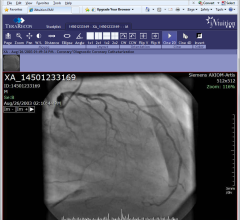

February 24, 2012 — TeraRecon Inc. highlighted the capability of its flagship iNtuition enterprise image management solution to image-enable the electronic medical record (EMR) at the annual meeting of the Healthcare Information and Management Systems Society (HIMSS), held Feb. 21-23, 2012, at the Las Vegas Sands Expo.